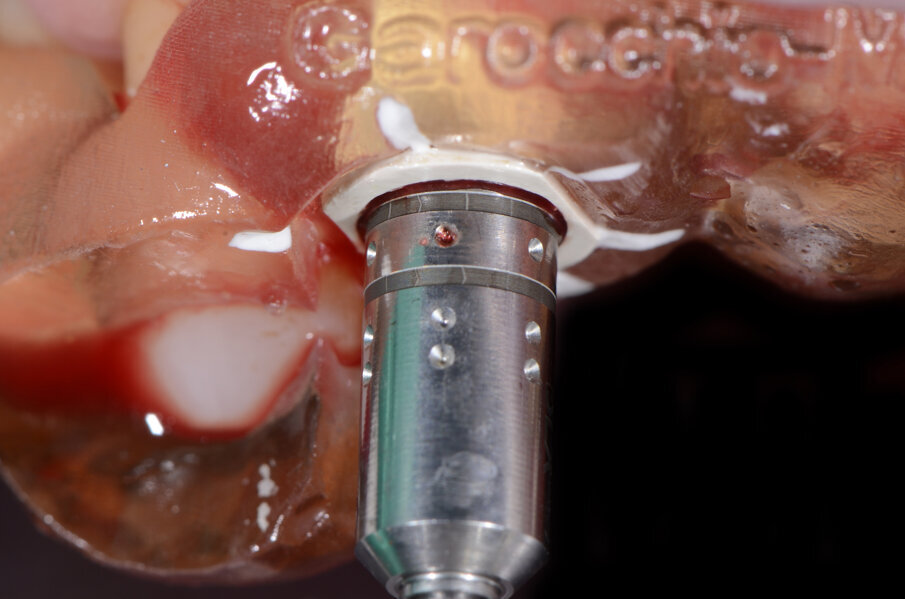

Il nostro obiettivo è quello di riuscire a dare alla paziente un provvisorio immediato nell’arco di due ore. Questo diventa possibile perché abbiamo utilizzato un flusso digitale fin dall’inizio. In laboratorio vengono realizzate la dima chirurgica (Figg. 16, 17), la dima protesica (Fig. 18) e anche il provvisorio (Figg. 19-21) che contiene delle alette di riposizionamento. Il tutto gestito con modelli digitali sui quali saremo in grado di funzionalizzare il provvisorio post-chirurgico (tecnica DIL). In un caso come questo se utilizziamo un flusso digitale possiamo evitare subito dopo la chirurgia di rilevare un’impronta degli impianti inseriti. Infatti, utilizziamo una dima chirurgica che ci faciliterà le fasi di intervento. La dima ci consentirà di non fare lembi e nessuna incisione di rilascio (Fig. 22), dopo aver inserito gli impianti (BLX Straumann) (Figg. 23-31) e aver controllato il loro alloggiamento, inseriamo sugli stessi dei transfert da impronta (Fig. 32).

Fig. 23- Posizionamento della dima.

Fig. 25 - Preparazione letto implantare.

Fig. 26 - Impianto BLX Straumann.

Fig. 27 - Posizionamento impianto 1.2.

Fig. 28 - Alloggiamento finale.